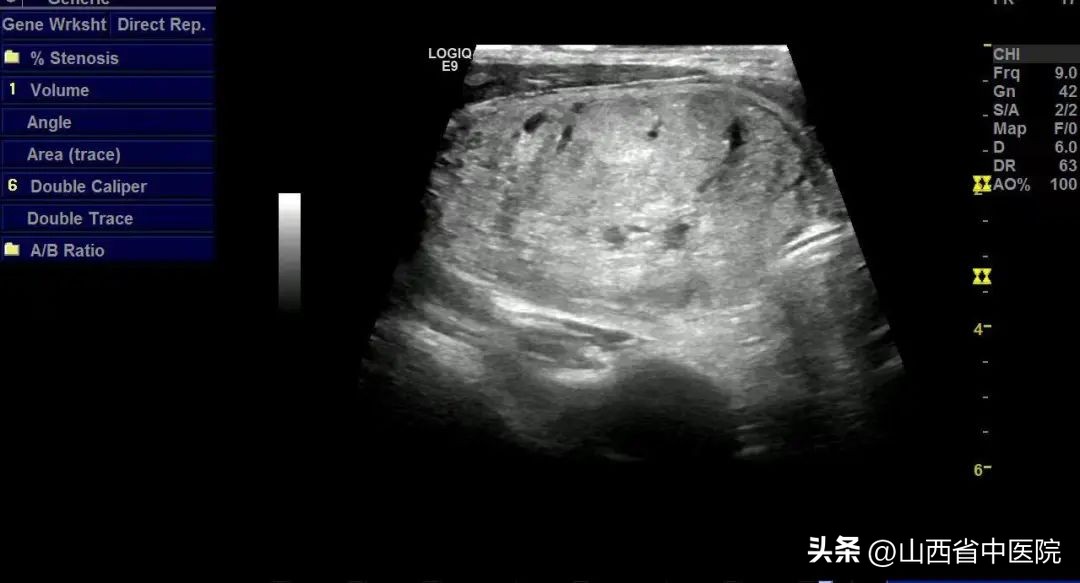

54岁赵先生,多年前发现双侧甲状腺多发结节TI RADS 3 类,因为惧怕甲状腺切除手术风险一直随访观察。但近年来,赵先生右侧的甲状腺肿物越长越大,有明显的吞咽异物感,轻度呼吸困难,且对周围器官形成压迫。2022年底再次复查彩超时,提示右侧甲状腺结节大小约为7.6*5.3*3.8cm,如同网球大小,肿物完全覆盖于气管表面,遂于各医院寻求治疗,因为外科手术切除,必须将一侧甲状腺切除,术后需要终身服药,因此赵先生和家人都比较排斥,希望医生能够尽量保留甲状腺功能。经人介绍,赵先生来到了山西省中医院寻求治疗,住院后,完善了相关检查。

(术前甲状腺结节,血供丰富)

(术前右侧甲状腺结节,对气管压迫,气管位于右下角)